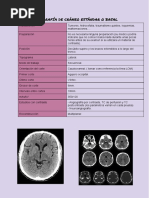

16 Fosa posterior y mesencéfalo

(a) – (h) Imágenes axiales de RM, de inferior a superior.

1 Nervio glosofaríngeo (NC IX) 5 Cuarto ventrículo 9 Protuberancia

2 Arteria basilar 6 Nervio vago (NC X) 10 Nervio abducens (motor ocular externo) (NC VI)

3 Agujero yugular 7 Hemisferio cerebeloso 11 Nervio facial (NC VII)

4 Bulbo raquídeo 8 Arteria carótida interna 12 Nervio vestibulococlear (estatoacústico) (NC VIII)

Las leyendas de las páginas 16-19 son comunes a las 4 páginas.